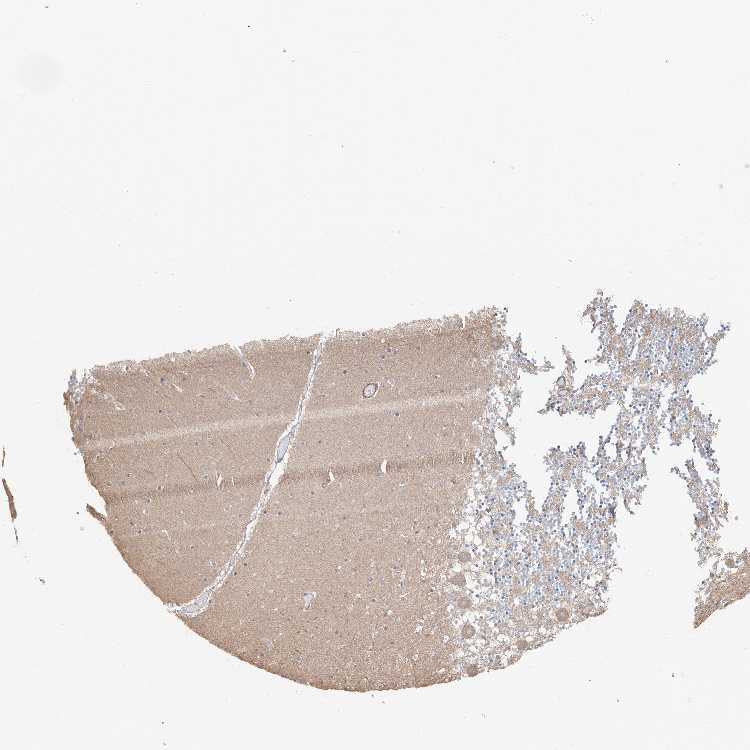

CEREBELLUM - Antibody stainingi

Antibody staining in the annotated cell types in the current human tissue is reported as not detected, low, medium, or high, based on conventional immunohistochemistry profiling in selected tissues. This score is based on the combination of the staining intensity and fraction of stained cells.

Each image is clickable and will lead to virtual microscopy that enables deeper exploration of all samples and also displays staining intensity scores, fraction scores and subcellular localization as well as patient and tissue information for each sample.

Antibody HPA031106Antibody HPA031107

Purkinje cells MediumNot detected

Cells in granular layer LowMedium

Cells in molecular layer LowLow